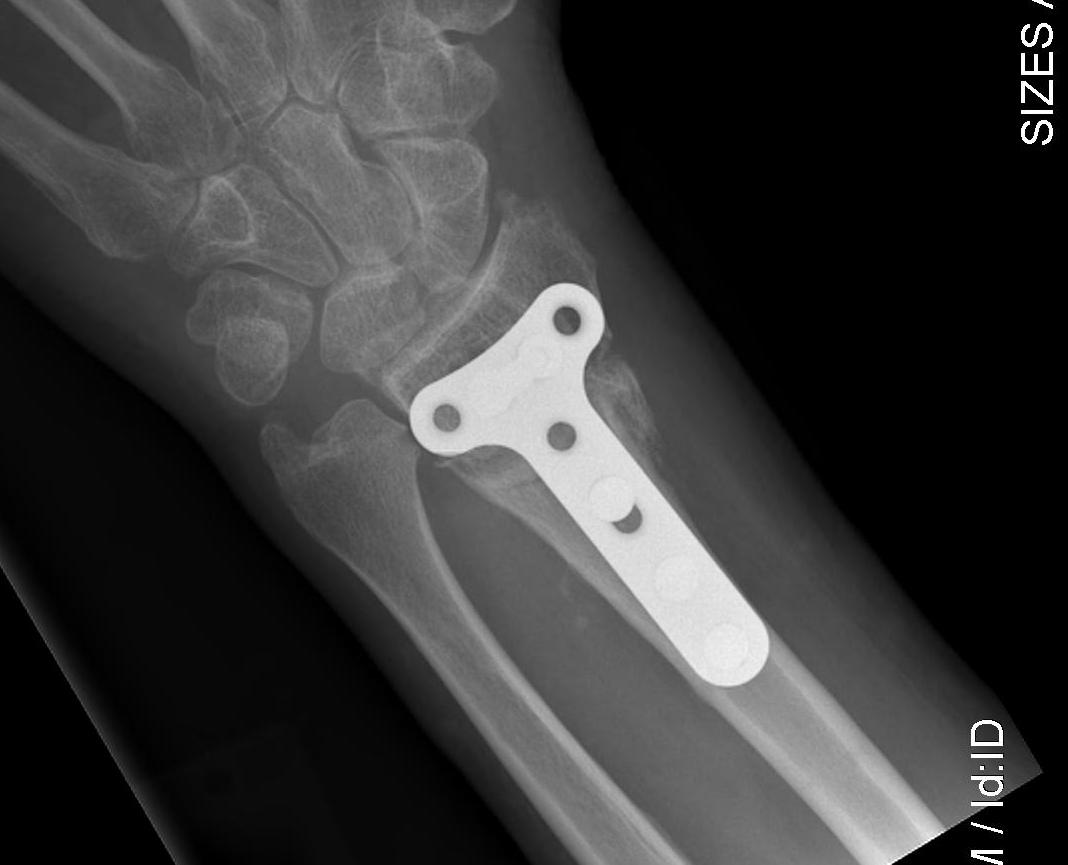

Volar opening wedge

Radial Malunion Volar Opening Wedge OsteotomyRadial Malunion Volar Opening Wedge Osteotomy Lateral

Advantage

Volar approach and plate

Technique

Bed of FCR approach

- release brachioradialis

- protect structures with retractors

- perform osteotomy parallel to articular surface

- sufficient distal bone for screw fixation

- correct distal radius in two planes

- apply volar plate

- bone graft defect through radial aspect of wound

+/- dorsal approach to insert bone graft

Volar osteotomyVolar osteotomyvolar osteotomyvolar osteotomy